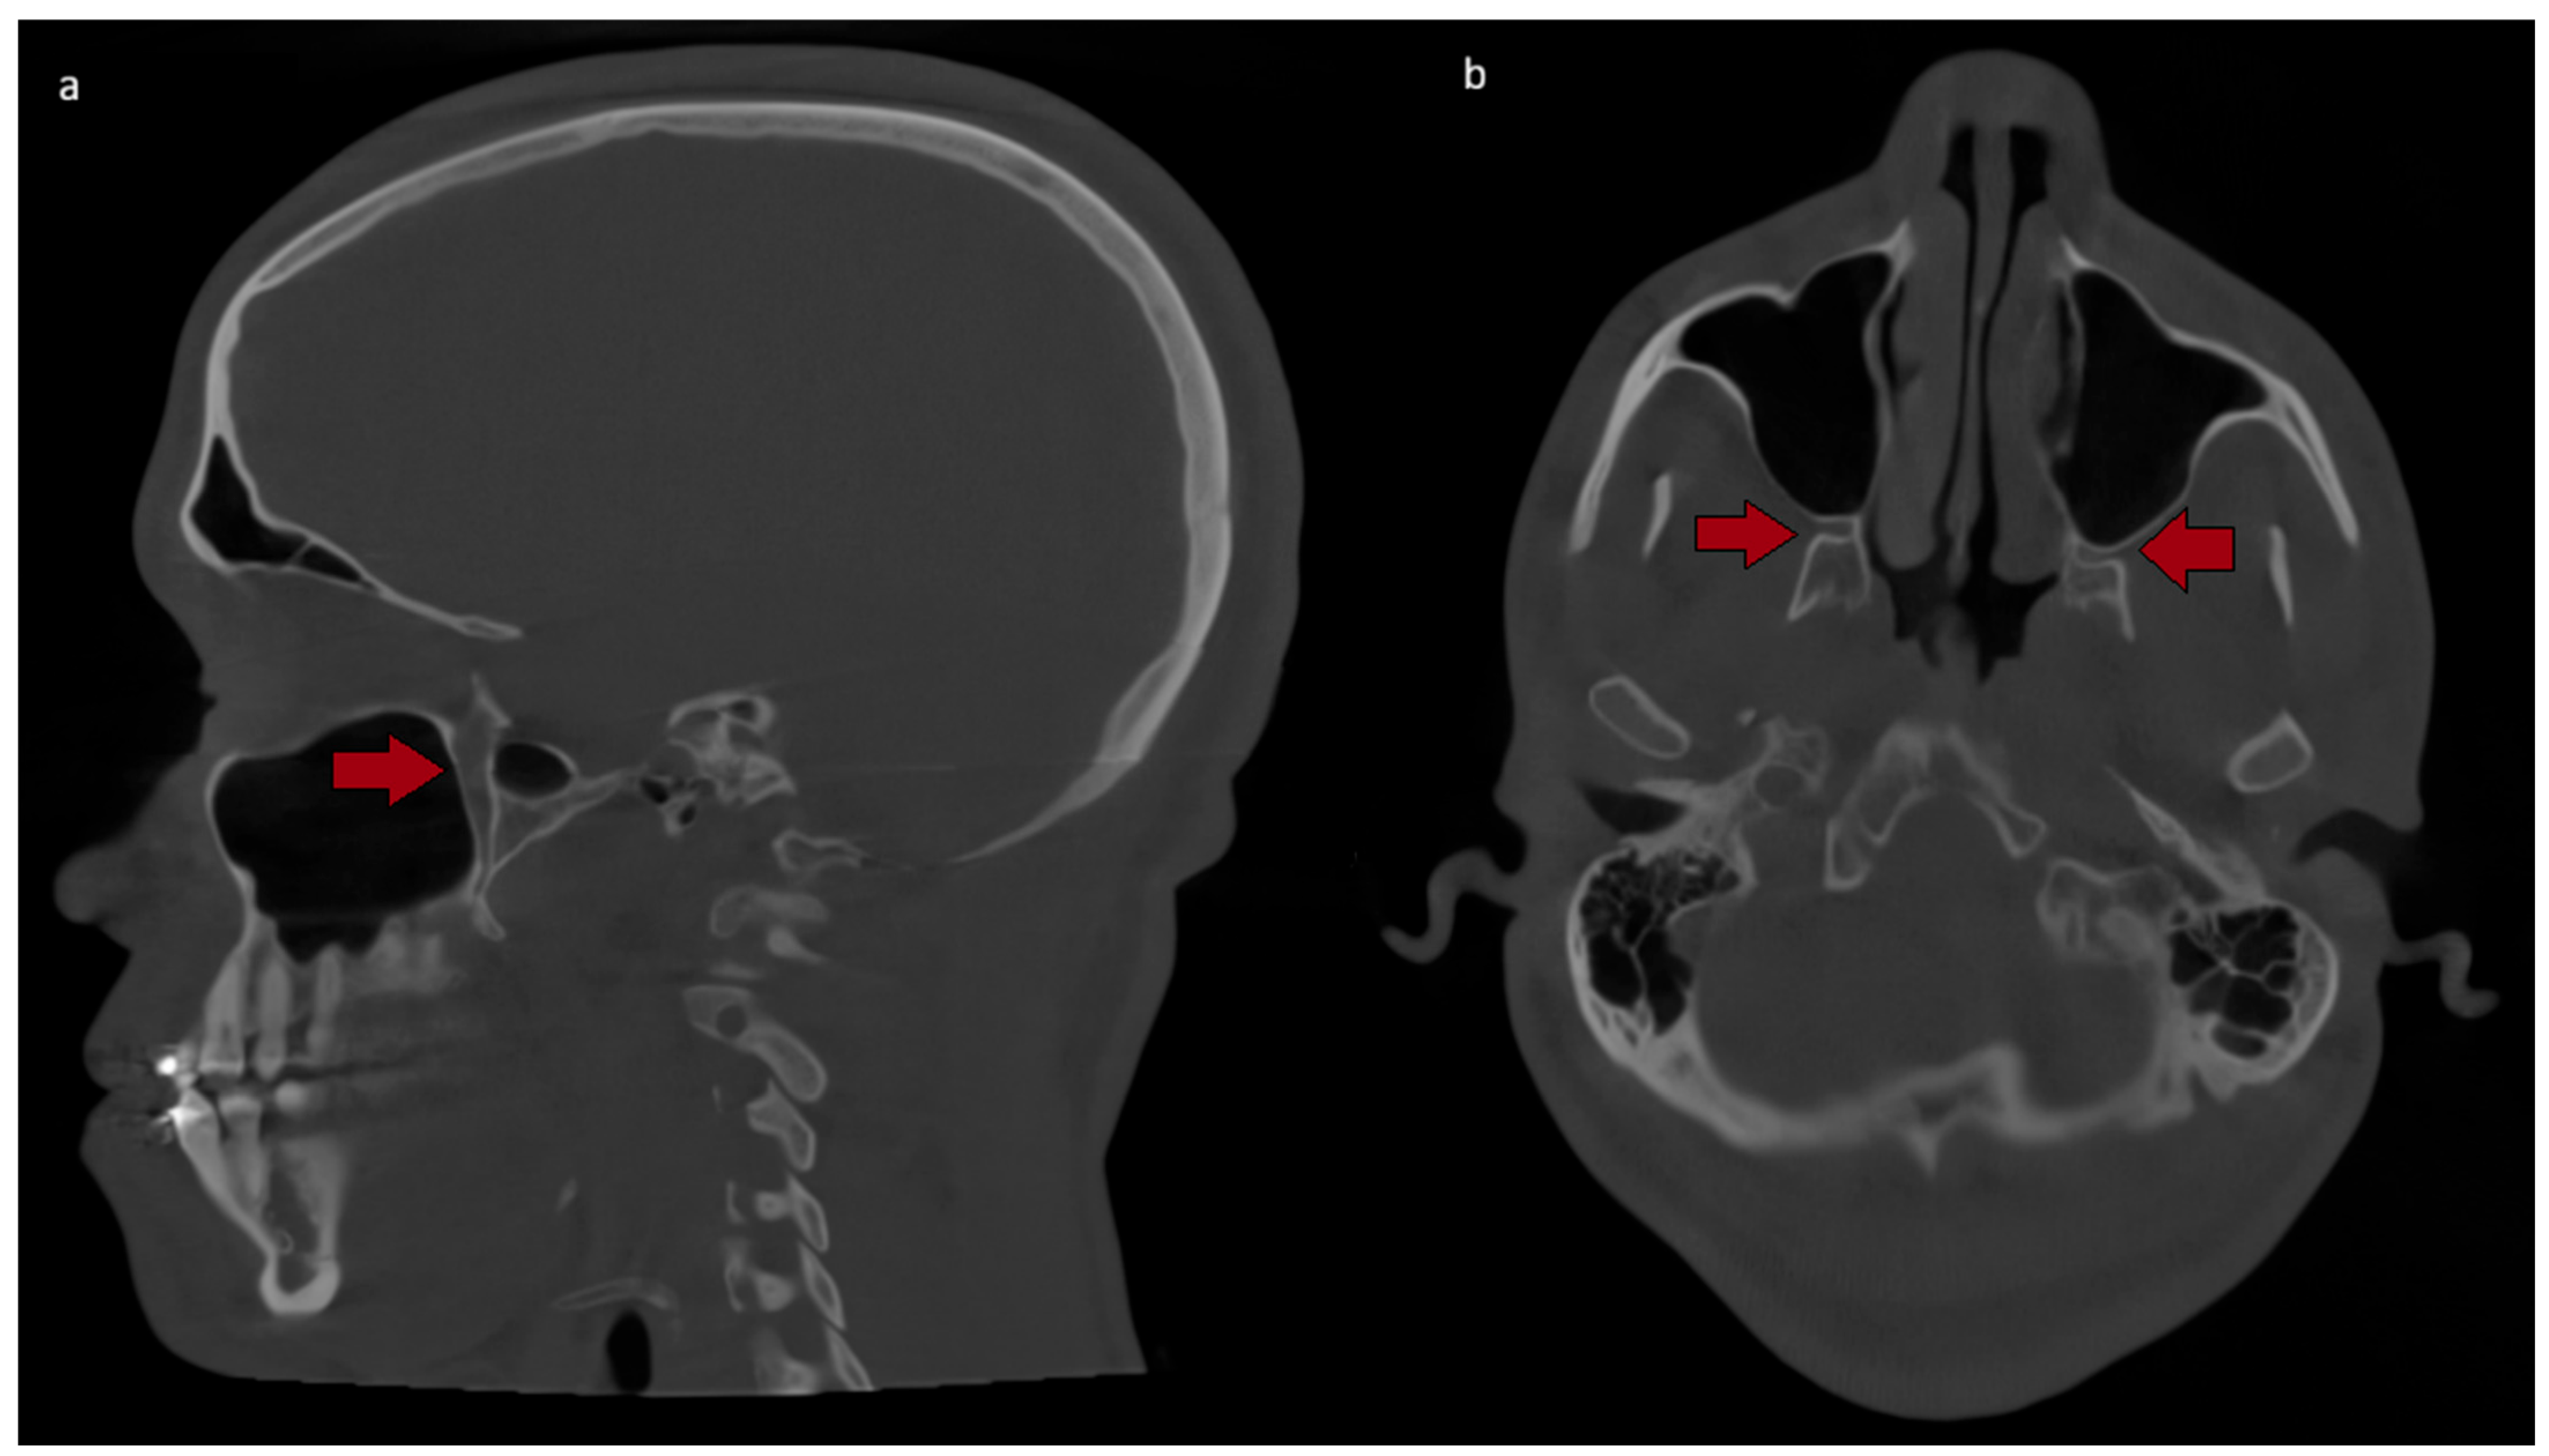

- Anticipate TCR during Le Fort I osteotomy: Surgeons should be aware that lateral nasal osteotomy, pterygomaxillary disjunction. Anticipate TCR during Le Fort I osteotomy: Surgeons should be aware that lateral nasal osteotomy, pterygomaxillary disjunction and maxillary down-fracture may elicit TCR-type events, particularly in young male patients. Anticipatory communication with anesthesia team is vital. Preoperative CBCT (Figure 1) can help visualize the posterior maxillary wall, pterygomaxillary junction, and their proximity to the pterygopalatine fossa, reinforcing awareness of this high-risk anatomic zone during planning and execution of the osteotomies.